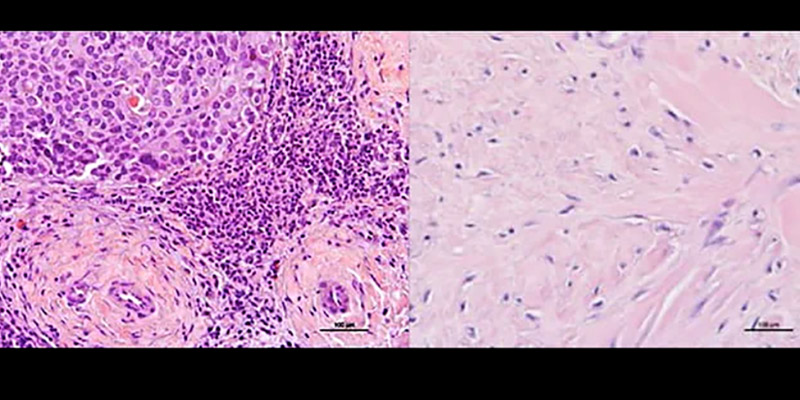

Un equipo de científicos del Hospital Houston Methodist ha dado un paso importante en la búsqueda de tratamientos eficaces para el cáncer de mama metaplásico (MpBC, por sus siglas en inglés), un tipo raro y altamente agresivo de cáncer de mama que representa menos del 5% de los casos, pero con el peor pronóstico entre todos los subtipos conocidos.

El MpBC se incluye dentro de los cánceres de mama triple negativos, lo que significa que no expresa receptores hormonales ni HER2, lo que limita enormemente las opciones terapéuticas. Además, su biología es particularmente agresiva: muchas de sus células tumorales están poco diferenciadas, lo que complica la respuesta a los tratamientos estándar.

En estos análisis, encontraron que dos vías celulares —la de NOS y la de PI3K— están activadas simultáneamente en el MpBC, algo que no ocurre en otros tipos de cáncer de mama. Esto sugiere que estas vías podrían estar trabajando juntas para favorecer la resistencia del tumor.

La inhibición de NOS con un compuesto llamado L-NMMA mostró resultados prometedores: las células cancerosas comenzaron a revertir su proceso de transición epitelio-mesenquimal (EMT), un cambio asociado con mayor agresividad e invasividad. Este fenómeno, combinado con inhibidores de PI3K como alpelisib y quimioterapia con taxanos, potenció la respuesta al tratamiento de forma significativa.